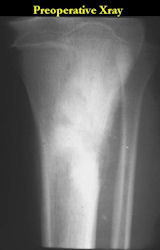

Gross Pathology: Osteosarcoma of Proximal Humerus

- originates from metaphysis of the proximal humerus, extends into surrounding soft tissues

- large soft tissue component that is crossing the glenohumeral joint

- was removed via an extra-articular resection, including scapula (Tikhoff-Linberg resection)